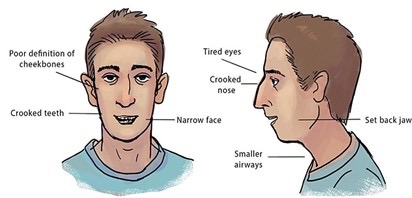

Myofunctional therapy is a program of specific exercises that target the facial muscles. The exercised-based therapy focuses on the mouth, tongue, and face muscles. These exercises are designed to develop, improve, and promote proper breathing, chewing, and swallowing. These exercises do strengthen the tongue. Below are frontal and side views of good normal growth and development of the orofacial structures.

Delayed Neuromotor Development: The abnormalities found in the orofacial muscles and structural differences can lend to some problems. This can be seen with the slow growth of the cheekbones and jaw.

Obstructive Airway: this could be from expanded tonsils, a deviated septum, or allergies. These issues effect the flow of air through the nasal airway. In turn, this can cause the jaw to change to an improper position causing adaptation to mouth-breathing since the nasal airway is obstructed.

Mouth-Breathing: This occurs when a person’s nasal passage obstructed thereby causing breathing from the mouth.

Malocclusion: Misalignment of the teeth causing crowding or no space for new teeth to erupt. This creates a poor bite.